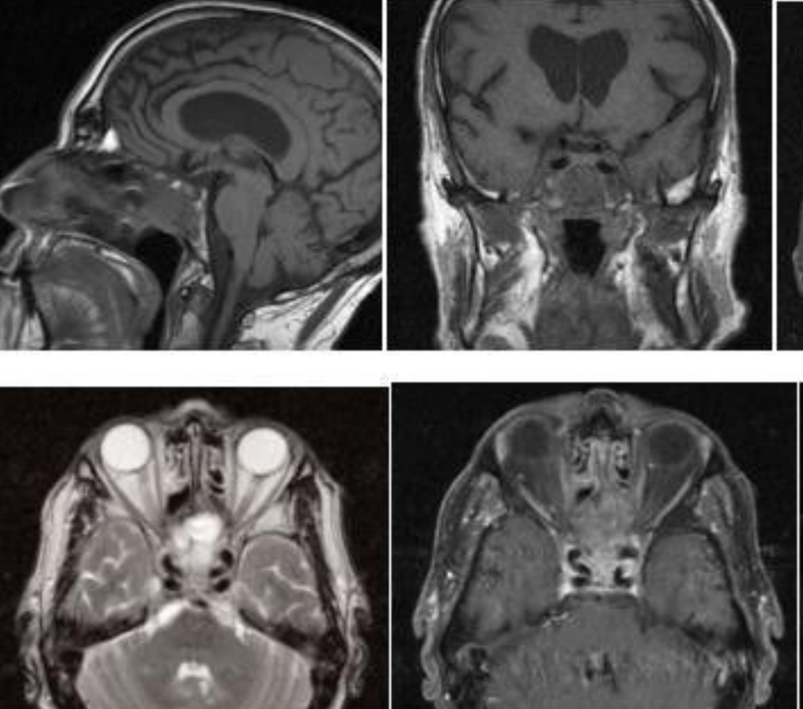

患者40+岁,女性,患者临床症状明显,近1年多来相继头痛、复视、肢体无力、吞咽困难等,当地医院诊断为较大斜坡脑膜瘤,辗转多地医院均告知肿瘤无法全切,术后并发症风险发生率高,后慕名咨询德国国际神经科学中心INI寻求巴特朗菲手术治疗,肿瘤切除97%以上,无相关手术并发症。

术前MR示:斜坡较大脑膜瘤,压迫脑干、颅神经,侵犯基底动脉等

术后MR显示:肿瘤近全切除,术后未见脑血肿、脑水肿,神经血管、脑干等组织保护完好。